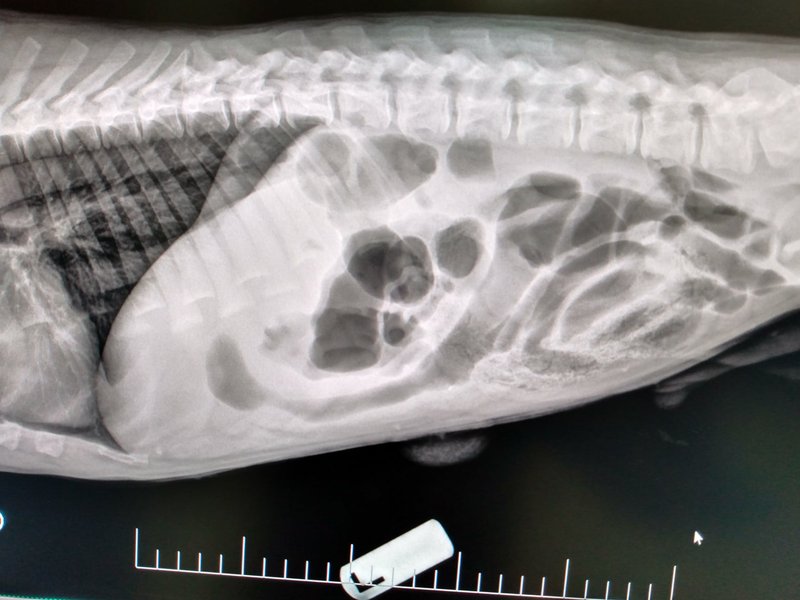

Ultrasound

Ultrasound is a non-invasive imaging tool that allows us to view your pet’s internal organs in real time. It is commonly used to evaluate abdominal structures such as the liver, kidneys, bladder, intestines, and spleen. In other situations, ultrasound may also be used to assess the heart or look for fluid within the chest or abdomen. This imaging tool provides detailed information about soft tissues and is often used alongside other diagnostics to help guide diagnosis and treatment planning.